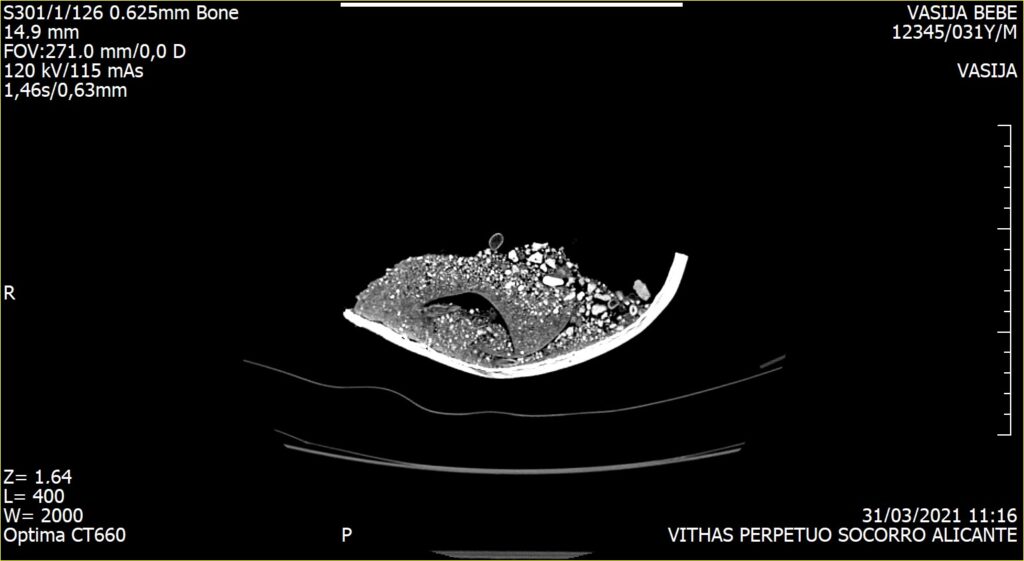

Debido a la fragilidad de los huesos se planteó la posibilidad de realizar un estudio radiológico que permitiría obtener la imagen del interior de la olla sin necesidad de ser excavada.

Este estudio, pionero en este tipo de enterramientos, fue realizado por el Hospital Vithas Alicante, quien puso a disposición de los arqueólogos, los mejores profesionales y los medios técnicos más avanzados para la consecución con éxito de esta tomografía computarizada aplicada a la Arqueología. Las pruebas practicadas revelaron que el cuerpo del perinatal se adaptaba a las paredes de la olla y que el cráneo se encontraba fracturado, quedando ambas partes solapadas.